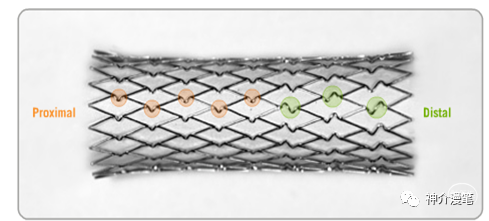

闭环支架的设计特点和开环支架刚好相反,所有的支架单元都呈现出连续封闭的状态,整个支架为一个连续完成的整体。其设计的特点使得其网眼更小,更利于提高局部金属覆盖率与对斑块的保护。但是其在迂曲血管的贴壁性会略差,同时因为其作为一个整体存在的特点,其趋势是使血管变直。因此对于血管走形的改变会略大。下图为闭环支架的设计特点,可以看到所有支架网格均为封闭连续的结构。

编织支架在不同管腔内会拉伸,并有释放后短缩现象。雕刻支架:金属圆筒由激光镂空雕刻形成,雕刻支架长度基本稳定,拉伸或短缩的现象极为少见。从结构特点上我们能知道,开环支架全部是雕刻支架,闭环则可能是雕刻也可能是编织。看过我这篇小豆腐块的同志,千万不要再从你们嘴里出现编织开环支架这个词了。下面第一个图,编织闭环支架,第二图为激光雕刻开环支架。